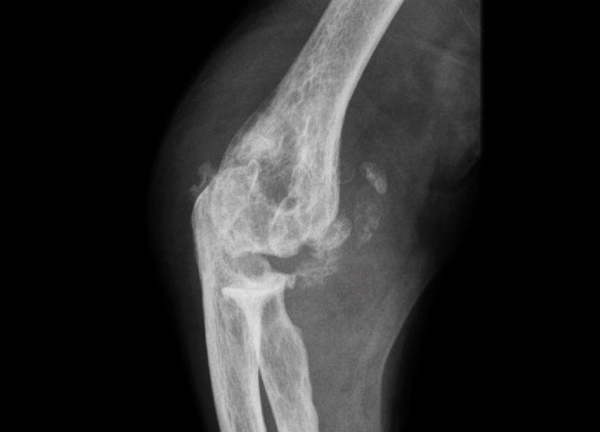

© Gérard Chalès, Pascal Guggenbuhl (La Revue du Praticien) Radiographie du coude (profil). Chondrocalcinose articulaire : arthropathie destructrice. Extrait de : Arthropathie microcristalline